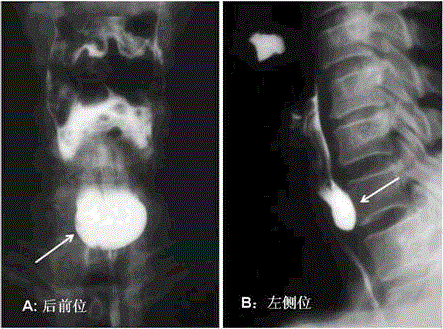

问题 患者女,30岁,数年来吞咽不适,有时可闻及“咕咕”声,并有吞咽困难,时常呃逆,口臭,行X线钡餐检查,结果如下图所示,应诊断为

选项 A、Zenker憩室 B、贲门失弛缓症 C、膈上食管憩室 D、食管癌 E、食管平滑肌瘤

答案 A